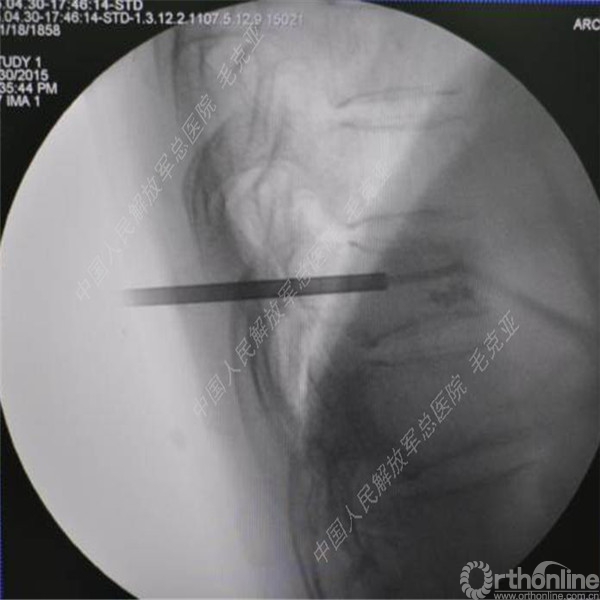

导语:随着社会老龄化的不断加速,骨质疏松性椎体压缩骨折作为一种普遍存在的老年骨科疾病已经成为现今骨科界的一个热点话题。传统的保守疗法治疗效果不佳,而现有的椎体增强技术又具有多种风险和缺陷。针对这种现状,中国人民解放军总医院毛克亚教授提供了一种新的解决方法。